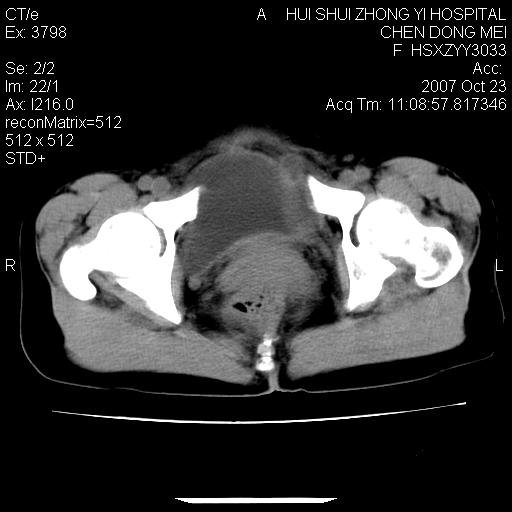

标题: CT10156:女.43岁,发现中下腹部包都块2年 [打印本页]

标题: CT10156:女.43岁,发现中下腹部包都块2年

发现中下腹部包都块2年。2年来月经不规律。

腹腔巨大软组织密度影,边缘光滑,包膜完整,内囊变坏死。腹膜后及盆腔内淋巴结肿大。结合病史考虑卵巢癌可能性大。

病变巨大,呈囊实性改变,包膜较厚且完整,内见分膈,周围脏器明显受压移位,病变与左侧附件关系密切,考虑来源左侧附件的囊腺瘤,不除外癌变可能;畸胎瘤可能性较小。

病变巨大,呈囊实性改变,包膜较厚且完整,内见分膈,周围脏器明显受压移位,病变与左侧附件关系密切,考虑来源左侧附件的囊腺瘤,盆腔内见肿大淋巴结,不除外癌变可能。